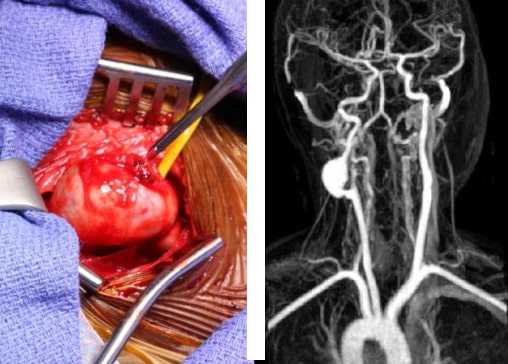

Операции проводились под общей анестезией. Первым этапом стандартным доступом выделялась бифуркация общей сонной артерии (ОСА). Параллельно производился забор лучевой артерии. Средняя длина шунта была 22,5 см. Диаметр в проксимальном отрезке составил от 2,5 до 3,4 мм, в дистальном отрезке - от 2,1 до 3,1 мм. После выполнения краниотомии выделялся М2 сегмент СМА, на него накладывались временные клипсы. Затем выполнялась продольная артериотомия М2 сегмента СМА, формировался дистальный анастомоз с дистальным отделом лучевой артерии по типу конец в бок (рис. 2). Клипсы с СМА снимались. Среднее время пережатия СМА составило от 35 до 44 мин. Шунт проводили в подкожном преаурикулярном тоннеле или под скуловой дугой в рану на шее.

Рис. 2. Формирование дистального анастомоза между М2 сегментом СМА и аутоартериальным шунтом.

После пережатия НСА формировался проксимальный анастомоз по типу конец в бок между начальным отделом НСА и графтом (рис. 3). После снятия зажимов проводился контроль кровотока по шунту и СМА с помощью допплерографии, флуометрии и видеоангиографии с индоцианиновым зеленым (ICG-VA) с временным пережатием ВСА в области устья (рис. 4). При сохранении адекватного кровотока по интракраниальным артериям выполняли лигирование ВСА в устье и ушивание операционных ран. В 1-е сутки после вмешательства всем больным выполняли контрольную МСКТ-ангиографию экстра- и интракраниальных сосудов (рис. 5). В ближайшие часы после операции ВСА в экстракраниальном отделе тромбировалась до уровня отхождения глазничной артерии без развития неврологической симптоматики (рис. 6).

Рис. 3. Формирование проксимального анастомоза между НСА и аутоартериальным шунтом. Рис. 4. Интраоперационный контроль (ICG-VA). Стрелкой указан дистальный анастомоз. Рис. 5. МСКТ-контроль дистального анастомоза. Стрелкой указан дистальный анастомоз между М2 сегментом СМА и аутоартериальным шунтом. Рис. 6. МСКТ-контроль после операции. Отмечается отсутствие контрастирования ВСА в экстракраниальном отделе. Стрелкой указан высокопотоковый экстраанатомический шунт НСА-СМА (High-flow EC-IC bypass).